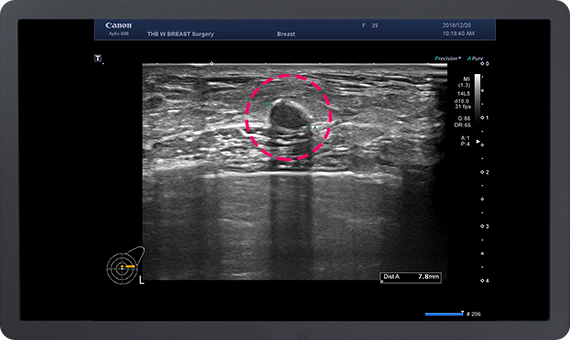

가슴지방 이식 수술 후 발생하는 가장 많은 부작용은

지방 낭종과 석회화입니다.

이에 대해 많은 경험을 가진 THE W 유방센터에서는

지방 이식 후 발생한 지방낭종과 석회화의 제거가 가능하며,

지속적인 유방암 추적이 가능합니다.